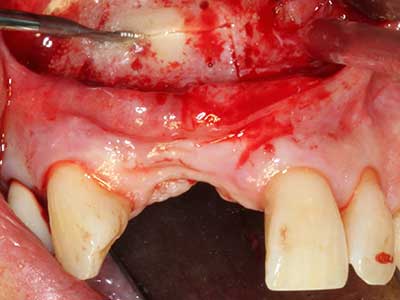

Come descritto in precedenza, le indicazioni per la piezochirurgia si possono trovare anche nel campo della chirurgia odontoiatrica conservativa. Delle puntine particolari semplificano l'esposizione delle punte delle radici e facilitano la protezione dei nervi e delle membrane mucose del seno, in particolare nella regione dentale superiore e posteriore e in quella premolare inferiore. Le puntine angolate diamantate si utilizzano per preparare con precisione la cavità della resezione che ospiterà il materiale di riempimento della radice retrograda per l'otturazione apicale sigillata. Grazie alla tecnologia a ultrasuoni le puntine possono essere estremamente sottili, quindi la visibilità e le dimensioni di accesso della cavità sono migliori. Di conseguenza, l'applicazione della chirurgia a ultrasuoni per questa indicazione è una delle procedure standard per la resezione apicale (Del Fabbro, Tsesis et al. 2010, Scarano, Artese et al. 2012).